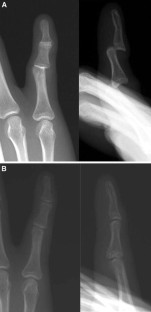

Simultaneous double dislocation of the interphalangeal joint in a finger

Isolated traumatic dislocation of the distal and proximal interphalangeal joints of the fingers is a common occurrence. However, simultaneous dislocation of both interphalangeal joints in a single finger appears to be a rare event. We report five cases of simultaneous dislocation of both interphalangeal joints in a single finger with a review of the literature.

Fig. 2